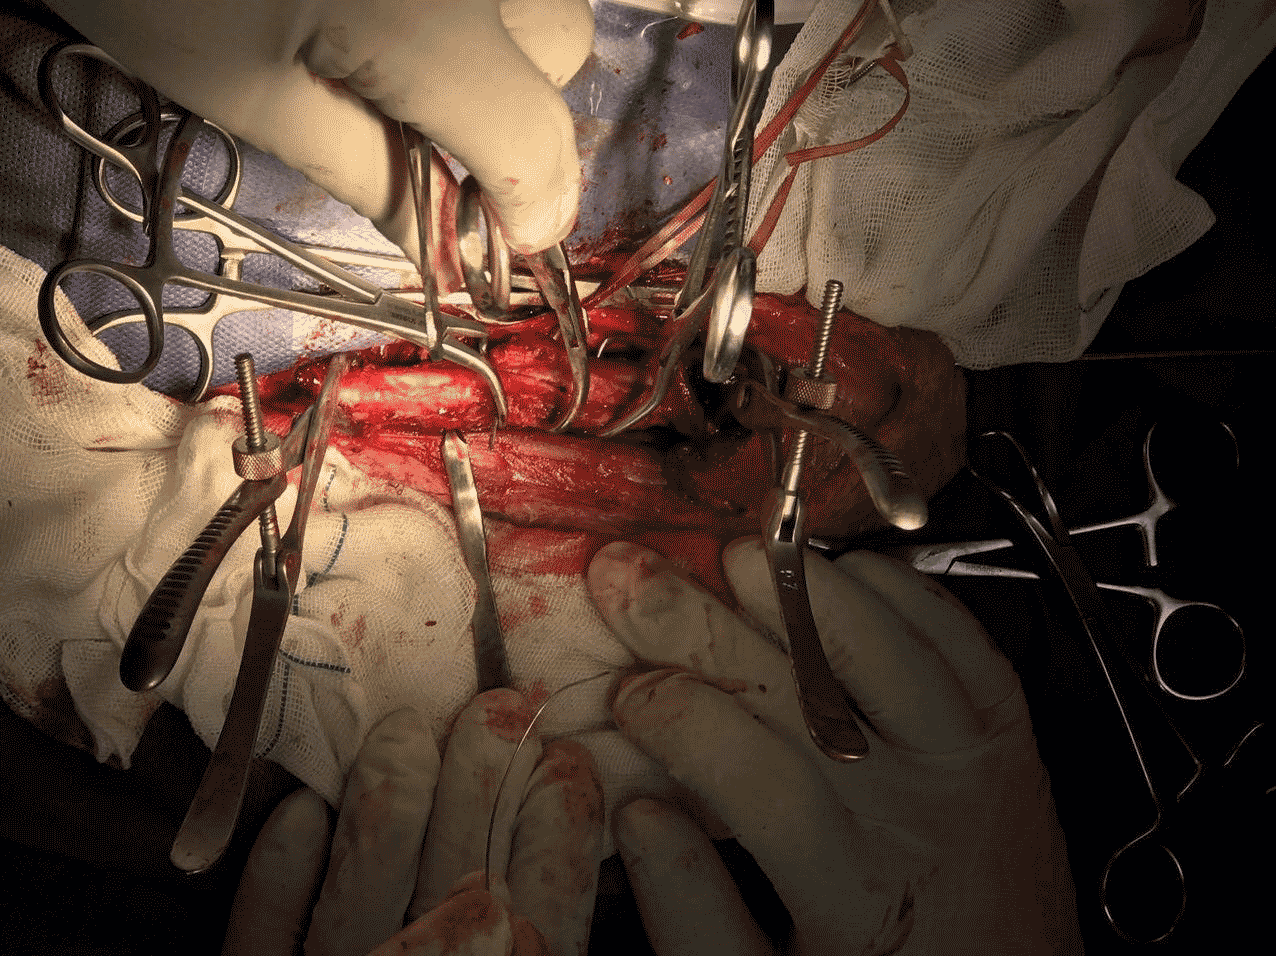

این دامپزشک یادآور میشود: طی این عمل با همکاری دو تن از همکاران، استخوان جوشخورده شکسته شده و بافتها و استخوانهای اضافه از اطراف عصب ردیال برداشته شد. و در نهایت دو لبه استخوان تمیز شد و کنار هم قرار گرفت. طی عمل جراحی وضعیت قلب، وضعیت تنفس و عمکرد دستگاه توسط سه متخصص مانیتور میشد. در این عمل روش Cerclage wire و IM Pinning مورد اسثفاده قرار گرفت. به علاوه دقت لازم اعمال شد تا بخشی از استخوانی که به کیسههای هوایی و ریه حیوان ارتباط دارد یا آسیب نبیند یا حداقل آسیب را متحمل شود.

وی به مراقبتهای دقیق انجام شده پس از عمل جراحی این عقاب شاهی اشاره کرده و میگوید: خوشبختانه این پرنده پس از 48 ساعت به تنهایی تغذیه را آغاز کرده و حال عمومی رضایتبخشی دارد. با گذشت سه روز از عمل جراحی، عقاب مجددا بیهوش شد تا زخم بررسی شود و مفصل بازو و آرنج تحت فیزیوتراپی قرار گیرد.